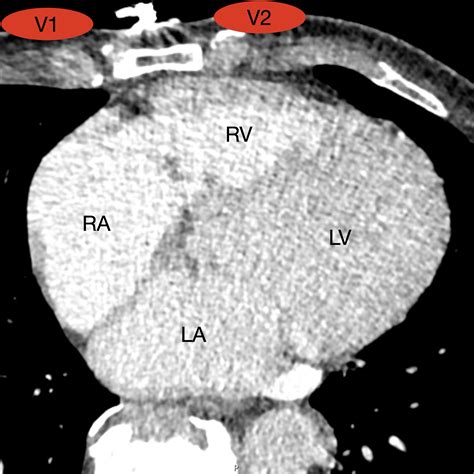

The 12-lead ECG is composed of three categories: limb leads (I, II, III, aVR, aVL, and aVF) and the six Precordial Leads (V1 through V6). While the limb leads provide a frontal plane view of the heart, the precordial set acts like a series of cameras placed strategically across the chest, capturing the electrical vectors moving toward or away from the front and lateral walls of the heart. These leads are essential for detecting electrical disturbances in the ventricular myocardium, providing insight that other leads simply cannot capture.

• V1: Fourth intercostal space at the right sternal border.

• V2: Fourth intercostal space at the left sternal border.